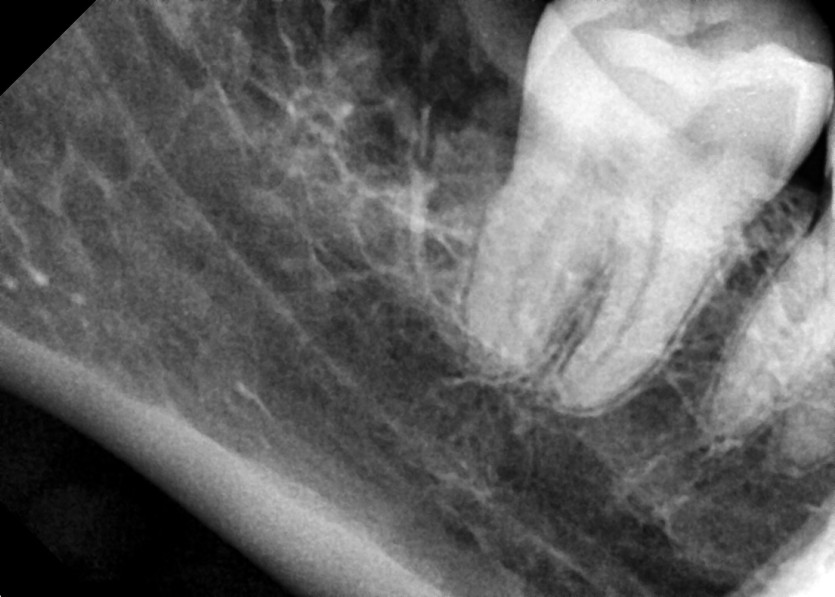

#18,28,38,48 사랑니 발치

구강 외과 전문의가 당일 발치했습니다.